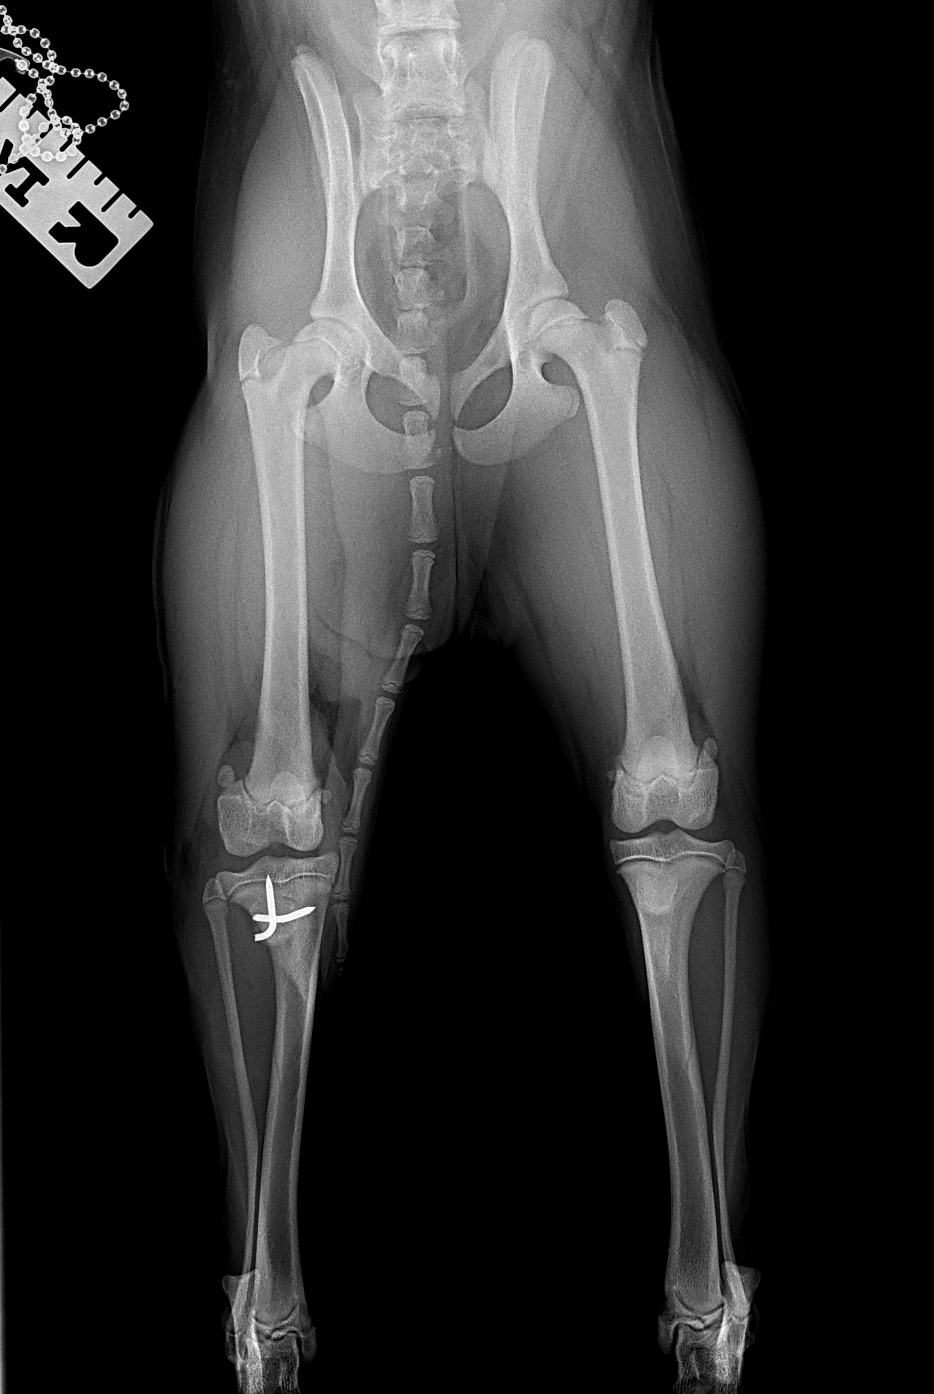

膝蓋骨内方脱臼G4

膝蓋骨内方脱臼G4により右後肢の負重が弱いという患者さんが紹介受診されました。膝蓋骨は大腿骨滑車から脱臼したままで大腿骨滑車内に誘導することができませんでした。大腿骨の変形などは幸い確認されませんでした。大腿骨滑車形成術、内側広筋の切離、脛骨粗面外側移行術、外側余剰関節包の切除によりアライメント手術を行いました。これから後療法も重要になります。